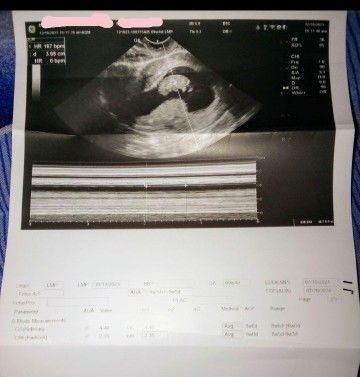

Hello mga sizt nka pag pa ultrasound na Ako yes kita kita ko na beby ko at na galaw n na sayaw pa dalawa paa nia at dalawa kamay nia .. yes .. po may heart beat na beby ko. 167 . Per minute heart beat nia .. ang linaw .. nag pa gawa KC Ako ng ultrasound ko KC para Malaman kung maselan Ako mg buntis .. actually.. good nmn ibig sabihin Hindi ... Ako maselan base sa ultrasound ko ang sa hula s ultrasound ko ang due-date ko .. July 20 2024. And base Naman sa last regla ko is July 19 2024 ... So sabi sakin ng o-b ko. Sa last regla ko raw ba basehin kung kailan ang xsaktong date sa dalawa so dipindi raw . #team July. 10;weeks and 2 days